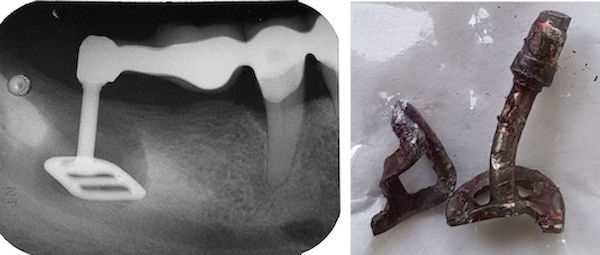

Bei diesem Fall besteht das Kauzentrum aus dem Implantat 3-i, den vier schwächsten Zähnen 21-12 und einem wurzelbehandelten Eckzahn -3. Diese beissen und kauen gegen eine Kompositbrücke mit Drahtverstärkungen (siehe hier)

Die Frakturgefahr entsteht nicht durch Bruxismus, sondern durch die geringe Grösse des Kauzentrums. Bei einem kleinen Kauzentrum werden die Zähne mechanisch gesehen gleich überlastet wie beim Bruxismus.

Nach einem Jahr ist beim Implantat +2i die Kompositfacette abgesplittert. Komposit klebt nicht an metallenen Implantat-Sekundärteilen. Deshalb wurde die Haftung mit einem zusätzlichen queren Draht und mit einem um Draht und Implantat herumgewickelten Ligaturendraht rein mechanisch verbessert.